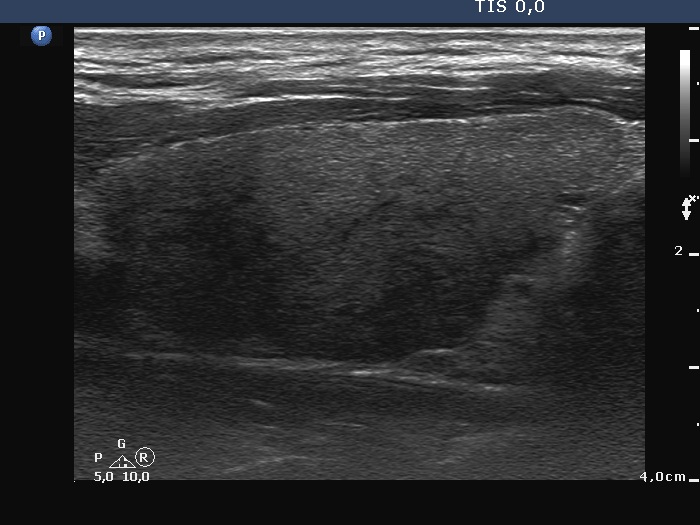

Examination 7 months later (second row of images):

Clinical presentation: The patient became asymptomatic within 12 hours after the first dose of methyl-prednisone and remained so.

Palpation: no abnormality.

Laboratory tests: TSH 1.03 mIU/L, FT4 14.2 pM/L, CRP 0.7 mg/L.

Ultrasonography: Both the size of the nodule and the extent of hypoechoic areas have decreased. An isoechoic nodule has appeared which was obscured by hypoechogenicity in the previous study. The vascularity was still very scanty.

Suggestion. Follow-up in 2 years.